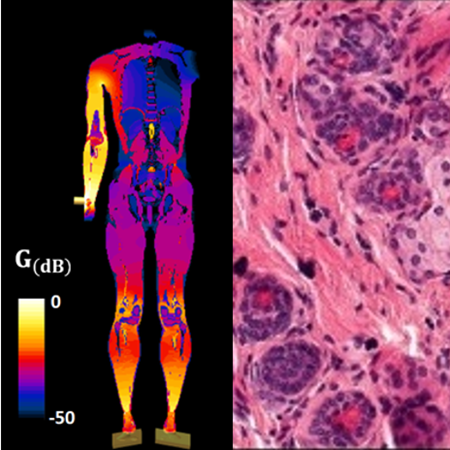

His current research focuses on cold plasma applied to life sciences, addressing cancerology (treatment of solid tumors like cholangiocarcinomas and non-small cell lung carcinomas), clinical engineering (cold plasma endoscopy), agriculture (seed decontamination, dormancy release, stimulation of seedling growth) and evolutionary biology (tardigrades, halites and diatomes). In parallel, he leads fundamental studies in plasma physics (guided streamers, self-organization). From his past experiences, TD also has a recognized expertise in plasma-material interactions (polymers, organometallics, colloids) and plasma gas processing (CO2 valorization, syngas production, micro-plasmas).

As of 2025, TD has authored 52 peer-reviewed articles and 12 conference proceedings, holds 6 patents, and has contributed to over 150 conference presentations. H-index : 25 (Google Scholar).

[05] Treatment of tumors by cold atmospheric plasma

– T. Dufour, M. Soulier, L. Fouassier, M. Camus

– Publication date: PI017101.FR (soumis en mars 2023)

[03] Outil pour dispositif de traitement médical par plasma et dispositif correspondant

– Inventors: T. Dufour, L. Fouassier, M. Camus, H. Decauchy

– Application number: WO2022229515 – Date of receipt: 03/11/2022 – N° of application: PCT/FR2021000041 – Date of publication of application: 28/04/2021 – Priority number: PCT/FR2021000041 – Priority date: 28/04/2021 – Classification CIB: A61B 18/04 – Classification CPC: A61B 18/042 – Patent family: WO2022229515A1

[01] Medical device for applying a plasma jet (Dispositif medical pour application de plasma)

– T. Dufour, L Fouassier, F Judée, S Pledel, J Vaquero

– N° of the application: WO2020254430 – Date of publication of the application: 24/12/2020 – Type of application: A1 – Filling number: PCT/EP2020066802 – Filling date: 17/06/2020 – Priority number: PCT/IB2019000782 – Priority date: 17/06/2019

[11] Treatment of carcinomas using atmospheric pressure plasma jets: from targets to in vivo models to investigate innocuity and therapeutic efficiency. T. Dufour, F. Judée, J. Vaquero, L. Fouassier. ISPC-24, Naples, Italy, 9-14 June 2019, proceeding Ref. 434. https://arxiv.org/ftp/arxiv/papers/1911/1911.10568.pdf